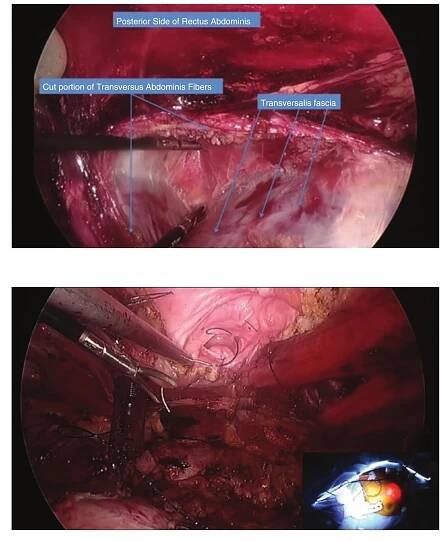

retromuscular sublay position. The developed retromuscular space is measured for appropriate mesh size selection. Our preference is medium weight macroporous polypropylene mesh which is deployed through our 12 mm trocar (Fig. 9.12). There is no need for antiadhesion barriers as there now exists an autologous barrier between the mesh and viscera, a significant advantage of the sublay position. Mesh placement in the retro- muscular space has allowed for the discontinua- tion of aggressive penetrating fixation techniques with transfascial sutures, transitioning first to fibrin glue and, more recently, to complete cessa- tion of mesh fixation as our data illustrates pene- trating fixation is associated with higher incidence of chronic pain without the added benefit of low-  ered rates of recurrence. Pneumoperitoneum is released under direct vision, assuring the mesh is lying flat and wrinkle-free between the posterior and anterior layers.  Formerly, we once placed drains just superfi- cial to the mesh in all repair cases. We are now more selective with drain placement and do not utilize it for most patients. To date, we have not observed an increase in wound morbidity as a result.  Formerly, we once placed drains just superfi-  there now exists an autologous barrier between